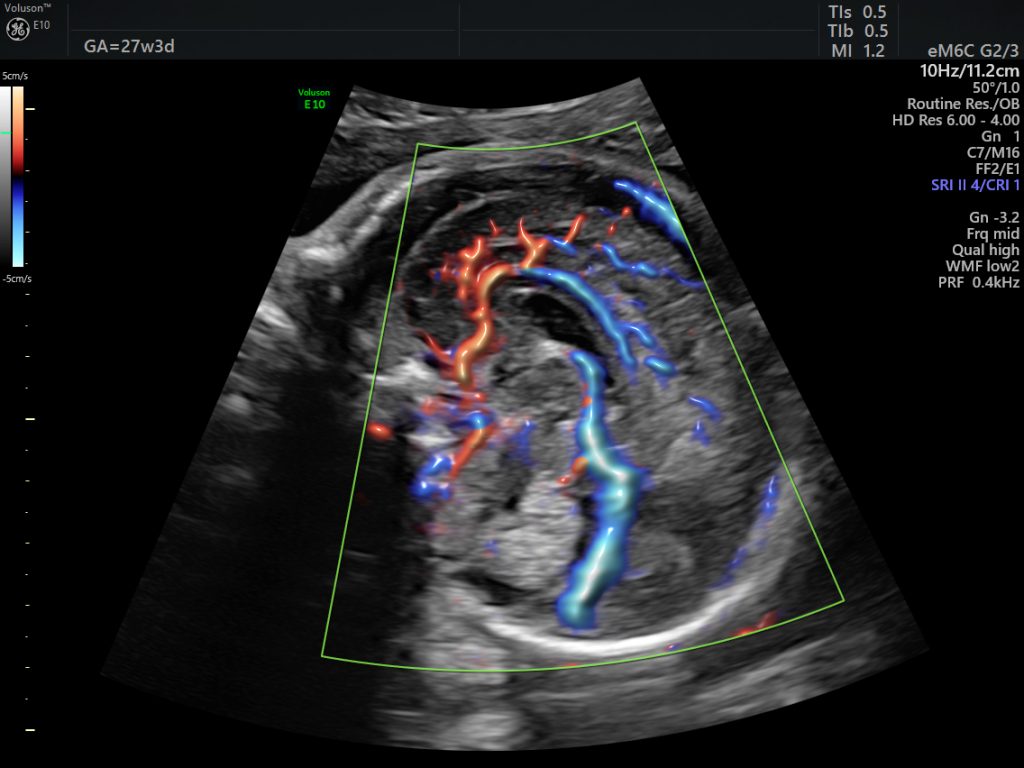

width= Fetal brain at 27 weeks. Image credit: GE Healthcare.